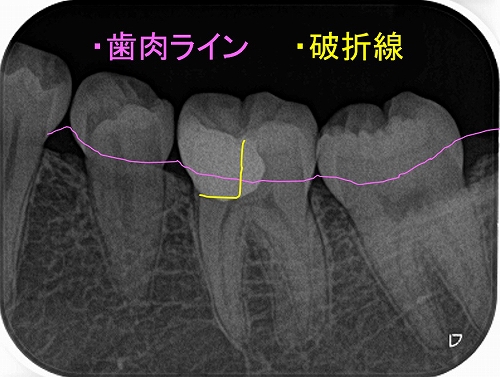

術前⇒術後

2026 EEdental NNS (5).jpg

レントゲン

2026 EEdental NNS (4).jpg

最後に咬合をチェックすると臼歯部に側方運動時のガイドがあり、

たぶん、昔もこのガイドが極端に強くて割れたんだろうなと推測。

2026 EEdental NNS (6).jpg

*最初の図と同じ割れ方になってました。

遠心にも似たようなガイドがあったので、最後に側方運動の咬合調整を行い終了となりました。